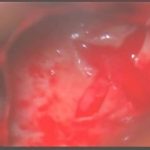

術中写真

摘出 前